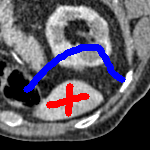

The motivation for this work comes from observing contradictions in using piecewise-constant intensity fitting terms in selective segmentation. Whilst good results are possible with this approach, the exceptional cases lead to severe limitations in practice. This is quite common in medical imaging as demonstrated in Fig. 1, where the target foreground has a low intensity. Given that the corresponding background includes large regions of low intensity, the optimal average intensities for this segmentation problem are and . For cases where , we see that by (1), almost everywhere in the domain . This means that it is very difficult to achieve an adequate result, without an over-reliance on the user input or parameter selection.

| (10) |

for and as defined in (33). This is consistent with respect to the intensities of the observed object and the concept of selective segmentation. In Fig. 3 we see the difference between CV and the proposed fitting terms for given user input on a CT image. For the CT image, the CV fitting terms are near 0 within the target region. This is despite there being a distinct homogeneous area with good contrast on the boundary. This illustrates the problem we are aiming to overcome. With the proposed fitting term this phenomenon should be avoided in cases like this. By defining as in (33) there is no contradiction if the foreground and background intensities of the target region are similar.